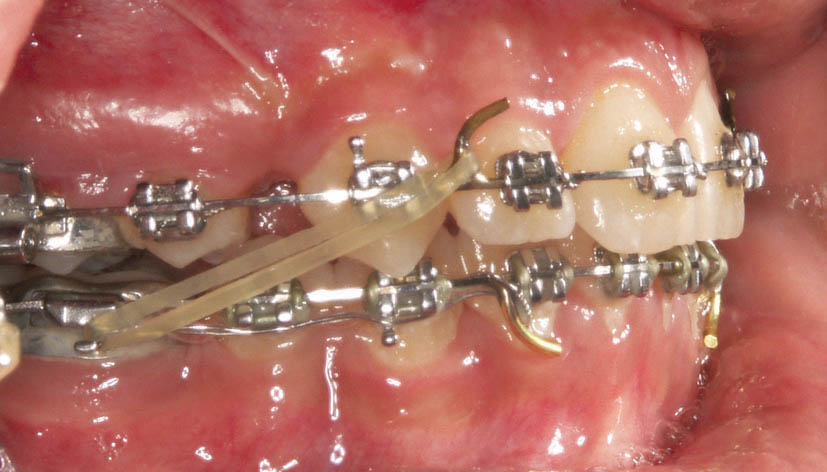

الاستیك كلاسII از هوك تیوب دندان 6 پایین به هوك آرچ وایر بالا متصل میگردد (شکل 178-1) و الاستیك كلاسIII از هوك تیوب دندان 6 بالا به هوك آرچ وایر پایین متصل میشود (شکل 179-1).

شکل 179-1: الاستیک کلاسIII